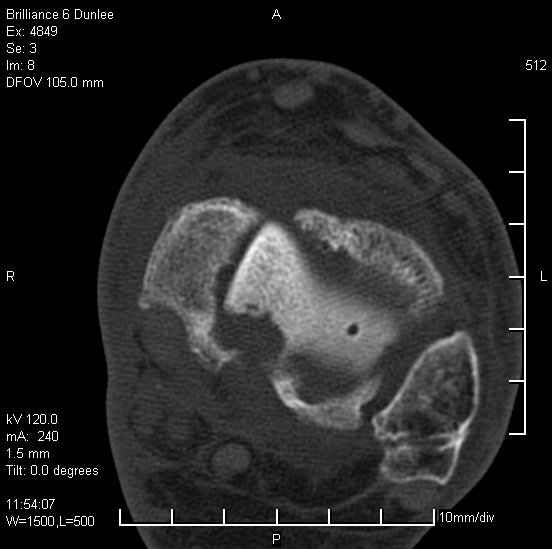

На лечении находится пациент 35 лет. Травма в сентябре 2008 г.- открытый вывих таранной кости

В день травмы ПХО, вправление вывиха, трансартикулярная фиксация. Рана зажила первично. С января нагрузка на конечность. С конца апреля- болевой синдром. На рентгенограммах и КТ признаки ас. некроза таранной кости, артроз подтаранного и голеностопного суставов.